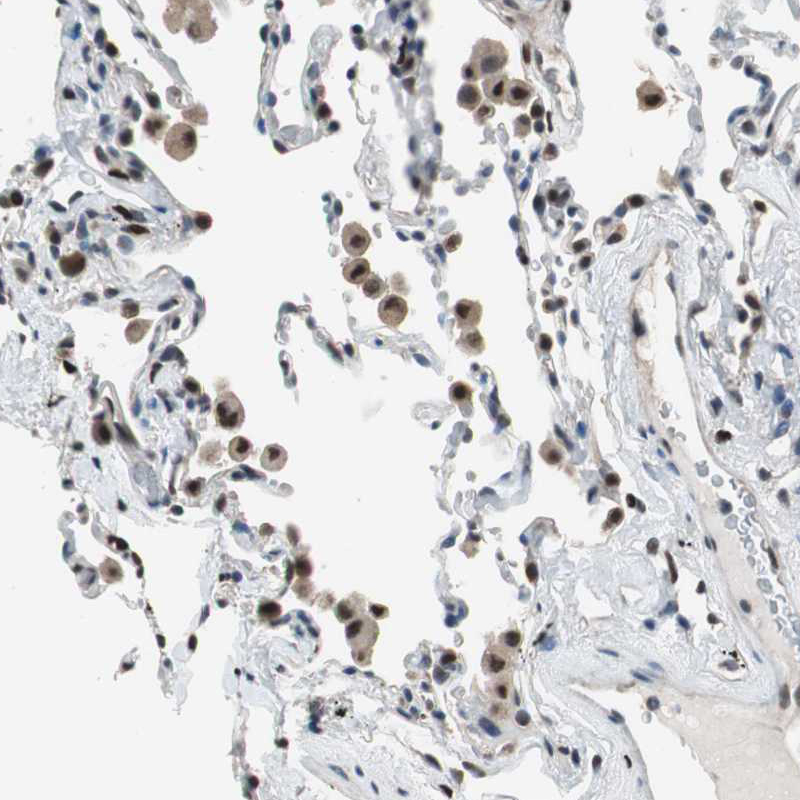

Immunohistochemical staining of human lung shows moderate to strong nuclear positivity in macrophages.